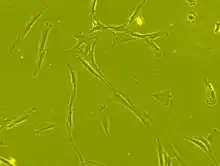

Mesenchymal stem cells (MSCs), a term first coined by Arnold I. Caplan in 1991,[10] are characterized morphologically by a small cell body with a few cell processes that are long and thin. The cell body contains a large, round nucleus with a prominent nucleolus, which is surrounded by finely dispersed chromatin particles, giving the nucleus a clear appearance. The remainder of the cell body contains a small amount of Golgi apparatus, rough endoplasmic reticulum, mitochondria, and polyribosomes. The cells, which are long and thin, are widely dispersed, and the adjacent extracellular matrix is populated by a few reticular fibrils, but is devoid of the other types of collagen fibrils.[11][12] These distinctive morphological features of mesenchymal stem cells can be visualized label-free using live cell imaging.

The International Society for Cellular Therapy (ISCT) has proposed a set of standards to define MSCs. A cell can be classified as an MSC if it shows plastic adherent properties under normal culture conditions and has a fibroblast-like morphology. In fact, some argue that MSCs and fibroblasts are functionally identical.[13] Furthermore, MSCs can undergo osteogenic, adipogenic and chondrogenic differentiation ex vivo. The cultured MSCs also express on their surface CD73, CD90 and CD105, while lacking the expression of CD11b, CD14, CD19, CD34, CD45, CD79a and HLA-DR surface markers.[14]